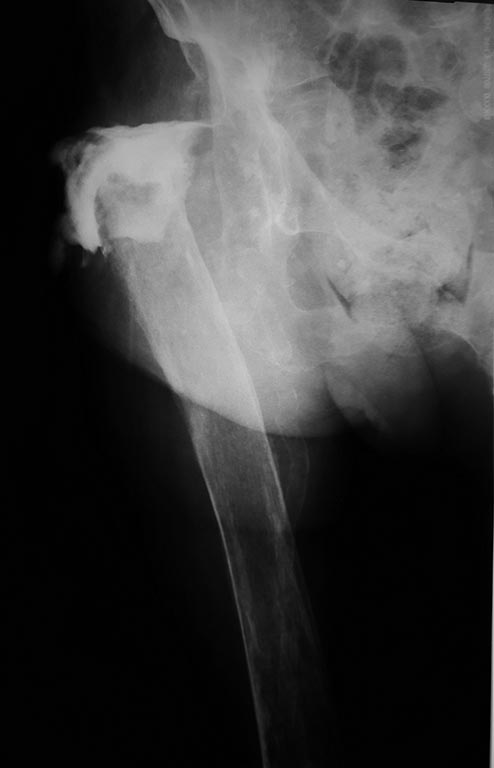

дальнейшего лечения. Больная, 85 лет, в стацинаре с 7.16г. по

поводу:Перипротезной инфекции, удаления эндопротеза тбс в 2014 году,

хр.остеомиелита правой бедренной коси и возможно костей таза,

свищевая форма. В 09.16 выполнена ревизия свища, санация, удаление

остатков цементной мантии из правой бедренной кости. Ведение раны

открыто до образования грануляций. в 11.16 выполнена вхо, вторичные швы.